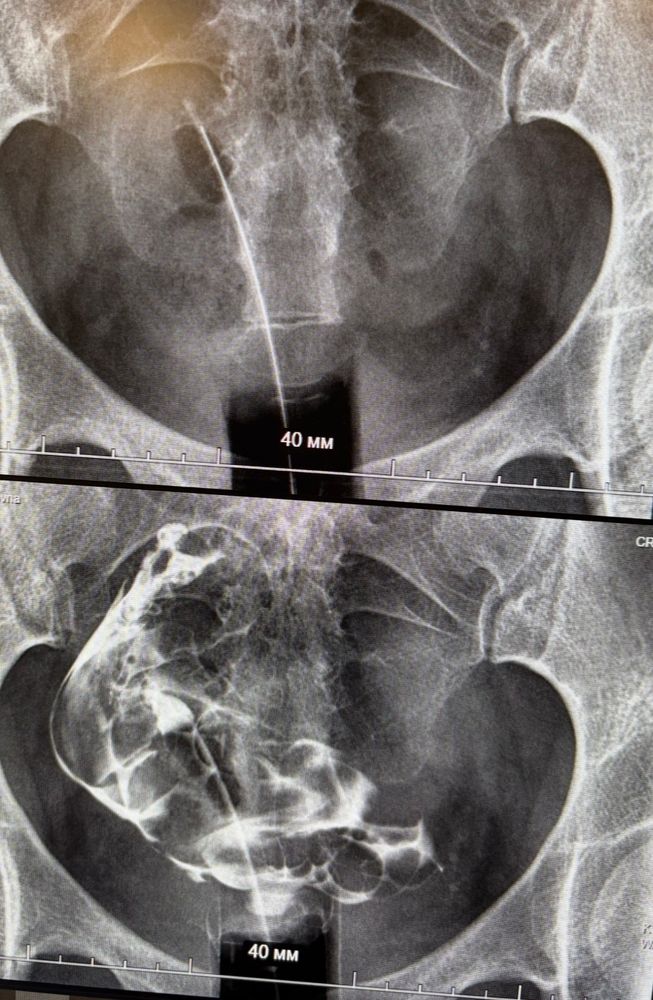

Однорогость по гсг и гистере

Матка сильно смещена. Это вообще бывает, у кого с такой патологией получилось? Я в эко. На гистере сказали матка норм размеров хотя бы.

У меня на снимке гсг матка лежит на девом боку. Очень сильно отклонена кзади и влево. Все ок) и еб были, и эко вот успешное тоже) она по мере беременности же будет растягиваться и расти. Мне сказали она после может выпрямиться и остатбся в норме, а может опять на бок лечь)

Пупа, можете у меня в дневнике найти пост с фото гсг. У меня сильно отклонена. Но честно, это меня не парило и не парит) просто крайний вариант нормы)

Аннэт, почитала что у вас седловидная. В целом это сформированный орган но с деформацией. А у меня однорогая и считается неполноценной(